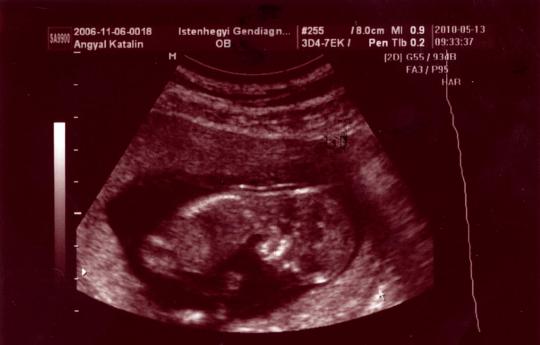

Ahogy a hasamra tette H.K. az uhu fejet, és megjelent a képernyőn a babóm, egyből mondta, hogy szép. A nagy kő legördült a szívemről. Aztán el kezdte méricskélni, és bólogatott nagyokat, és az arcán is láttam a nyugodtságot. Tarkóredőt 1,8 és 1,8-nek mérte, orrcsont is van. A végén azt mondta, hogy teljesen negatív uh alapján, de azért megkérdezte, hogy akarok-e amniócentézist, vagy inkább megszülöm (itt gondolom, a vetélési kockázatra gondolt). Aztán a véreredmény is nagyon jó lett, minden az értékeken belül. A PAPP-A 1,00 MoM, a BHCG 1,66 MoM. Így a két kockázati tényezőmmel együtt (korom + korábbi Down-kór) magasan negatív lett az eredményem, 1:1060-hoz. Ha kivették volna a down kockázatott, közel 1:2000-hez lett volna.

Ma beszkenneltem a babókám képeit, és gondoltam, veletek is megosztom:

Kép

Sajnos a nemét esélyünk sem volt megnézni, mivel végig hason volt, hiába bökdöstük, csak félig volt hajlandó megfordulni, és kibújni a lepényből, és akkor is takargatta a kis ökleivel az arcát. Érdekes, a fiam sosem volt szemérmes az uh-kon :roll:

A mért méretek alapján teljesen megfelel a terhességi kornak, 12+4 (és valóban 1-2 nappal kisebb a baba, mint amit a vonalzóm jelez, mert a 15. vagy 16. napon fogant). 7,04 centis az Óriásgombockám.